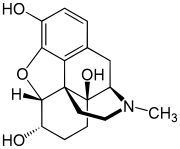

Morphinones and morphols

- 14-Cinnamoyloxycodeinone

- 14-Ethoxymetopon

- 14-Methoxymetopon

- 14-Phenylpropoxymetopon

- 3-Acetyloxymorphone

- 3,14-Diacetyloxymorphone

- 7-Spiroindanyloxymorphone

- 8,14-Dihydroxydihydromorphinone

- Acetylcodone

- Acetylmorphone

- α-hydrocodol (=dihydrocodeine, )

- Benzhydrocodone

- Bromoisopropropyldihydromorphinone cas?

- Codeinone

- Codoxime

- Conorfone (codorphone)

- IBNtxA

- Thebacon (acetyldihydrocodeinone, dihydrocodeinone enol acetate)

- Hydrocodone

- Hydromorphone

- Hydroxycodeine

- Metopon (=methyldihydromorphinone)

- Morphenol

- Morphinone

- Morphol

- N-Phenethyl-14-ethoxymetopon

- Noroxymorphone

- Oxycodone

- Oxymorphol

- Oxymorphone

- Pentamorphone

- Semorphone

Structures